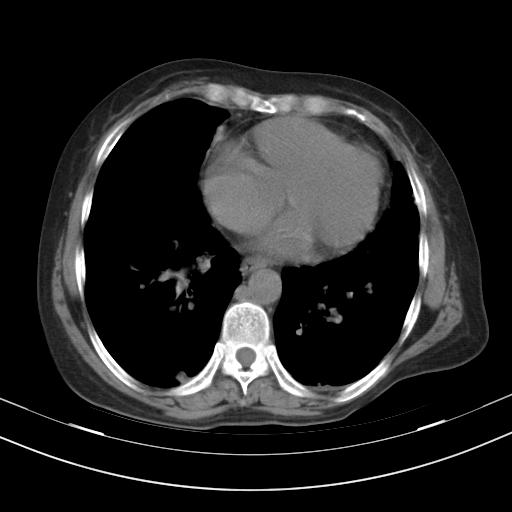

老年女性,嗜睡3天,意识模糊。轻咳,无发热。

1)两肺感染性病变;建议抗炎治疗后复查。2)纵隔淋巴结肿大。3)左侧胸腔积液。

1)先考虑两肺感染性病变;建议抗炎治疗后复查。

2)纵隔淋巴结肿大。

3)左侧胸腔积液。